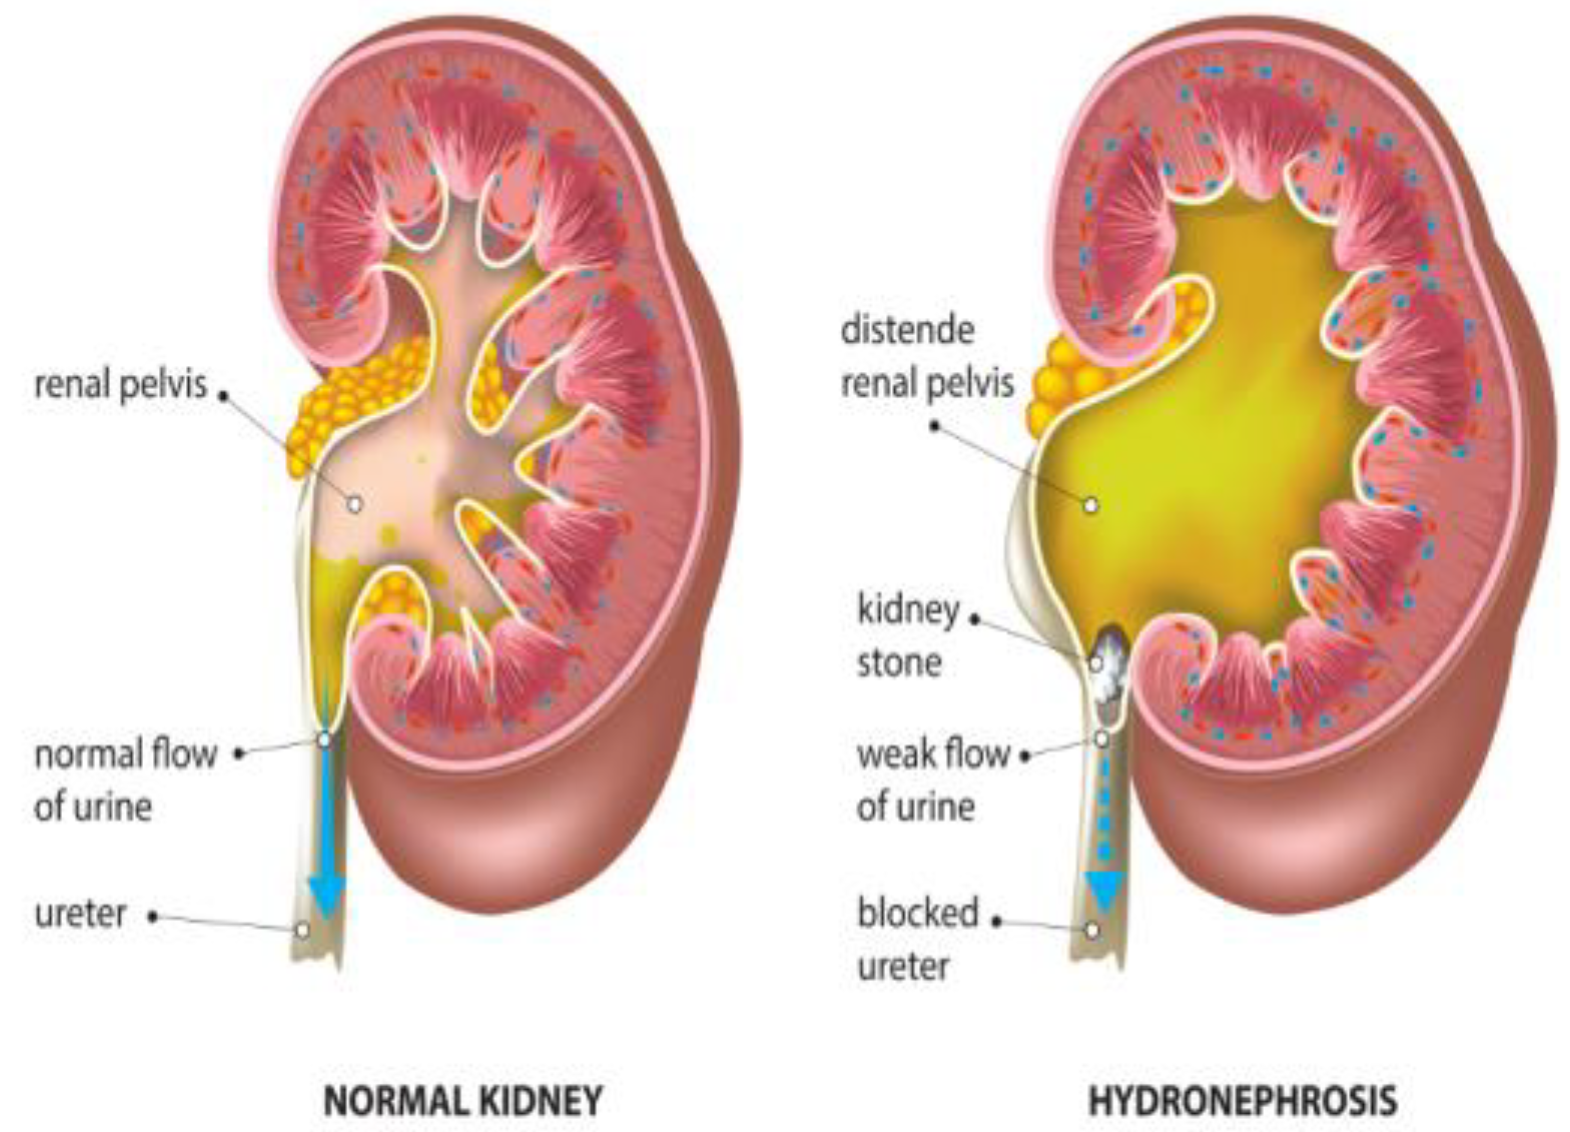

2.1. Diagnostic Challenges in Pediatric Hydronephrosis

| Subjective nature of ultrasound imaging [24] | Traditional methods for diagnosing pediatric hydronephrosis rely heavily on ultrasound imaging, which is subjective and prone to variability. | Implementing DL models can offer more impartial and replicable diagnostic tools, reducing the subjective and variable nature of ultrasound interpretation. |

| Issues with imaging techniques [20] | Although imaging techniques like abdominal CT are efficient, they pose risks of radiation exposure and higher cost. | Exploring alternative imaging modalities with lower radiation exposure, such as magnetic resonance urography (MRU), can mitigate the risks associated with radiation exposure while maintaining diagnostic efficiency. |

2.2. AL Solutions for Hydronephrosis Management

2.3. Impact on Treatment Planning and Long-Term Monitoring